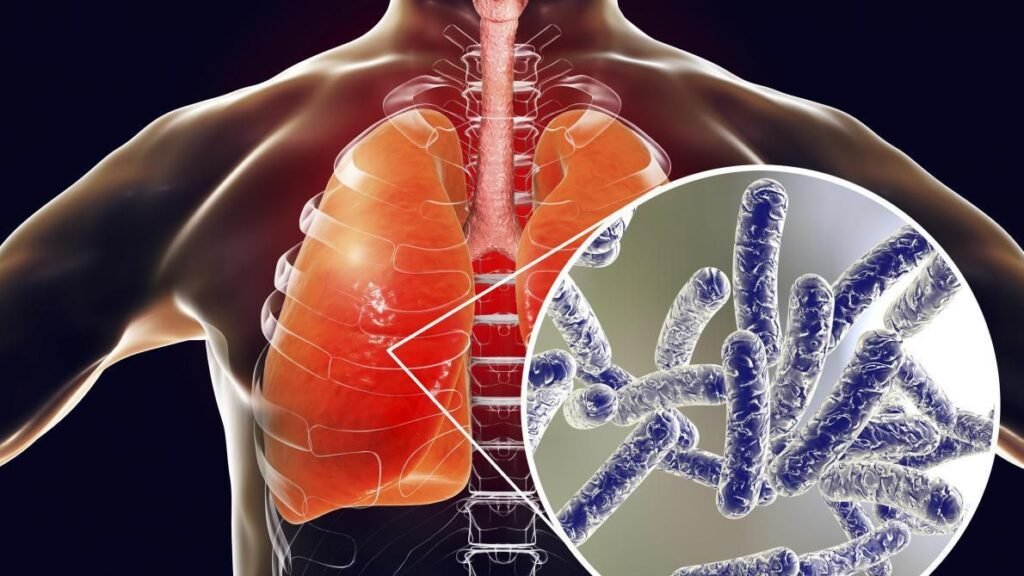

Туберкульоз — це хвороба, яку викликають бактерії, що найчастіше уражають легені, але водночас можуть вражати кістки, нирки, мозок та інші органи, і саме тому її важливо сприймати серйозно та відповідально.

Туберкульозз буває легеневим і позалегеневим, і хоча легенева форма зустрічається найчастіше, інші форми також небезпечні та потребують лікування під наглядом спеціалістів.

Туберкульозз легенів проявляється поступово, і тому людина може довго не помічати серйозних змін, що, у свою чергу, ускладнює ранню діагностику.

Позалегеневий туберкульозз може вражати кістки, суглоби, лімфатичні вузли або мозок, і хоча він менш заразний, він все одно потребує тривалого та системного лікування.